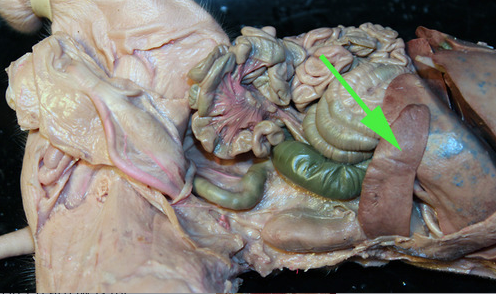

Areas of diffuse lymphatic tissue are found in the walls of the structures marked by the green arrows. They are called the///small intestine

The diffuse lymphatic tissue found in the structure marked by the green arrow is called peyer's PATCH

The green arrow is indicating the peyer's patch in this area of the small intestine. It is made up of a dense accumulation of what kind of cells?//lymphocytes

diffuse lymphatic tissue called peyer's patches in the wall of the intestinal tract.